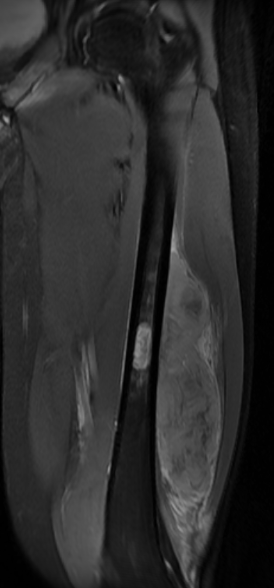

MRI

Low signal intensity of T1 / high signal intensity on T2

- intramedullary extent

- skip lesions

Significant soft tissue mass with significant edema

Pathological fracture with skip lesion

Ewing proximal femur

Ewing's humerus

Ewing's femoral diaphysis, subtle on xray with large soft tissue component

Ewing's distal femur

Ewings iliac crest